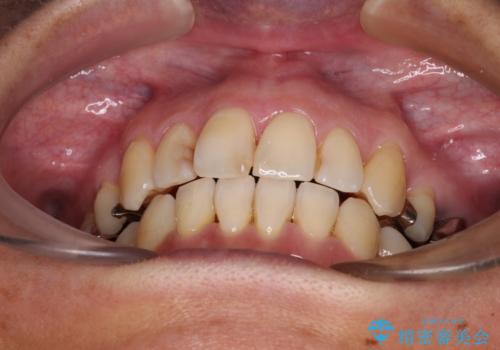

- 八重歯と、それによる口元の膨らみを気にして来院された患者様です。

八重歯・デコボコの解消とともに、前方に張り出した上顎前歯を引っ込めることを目的とし、上下左右の第一小臼歯4歯を抜歯をしてワイヤー矯正により治療することとしました。

半年もしないうちに八重歯は解消し、治療も当初予定通り2年強で終えることができました。